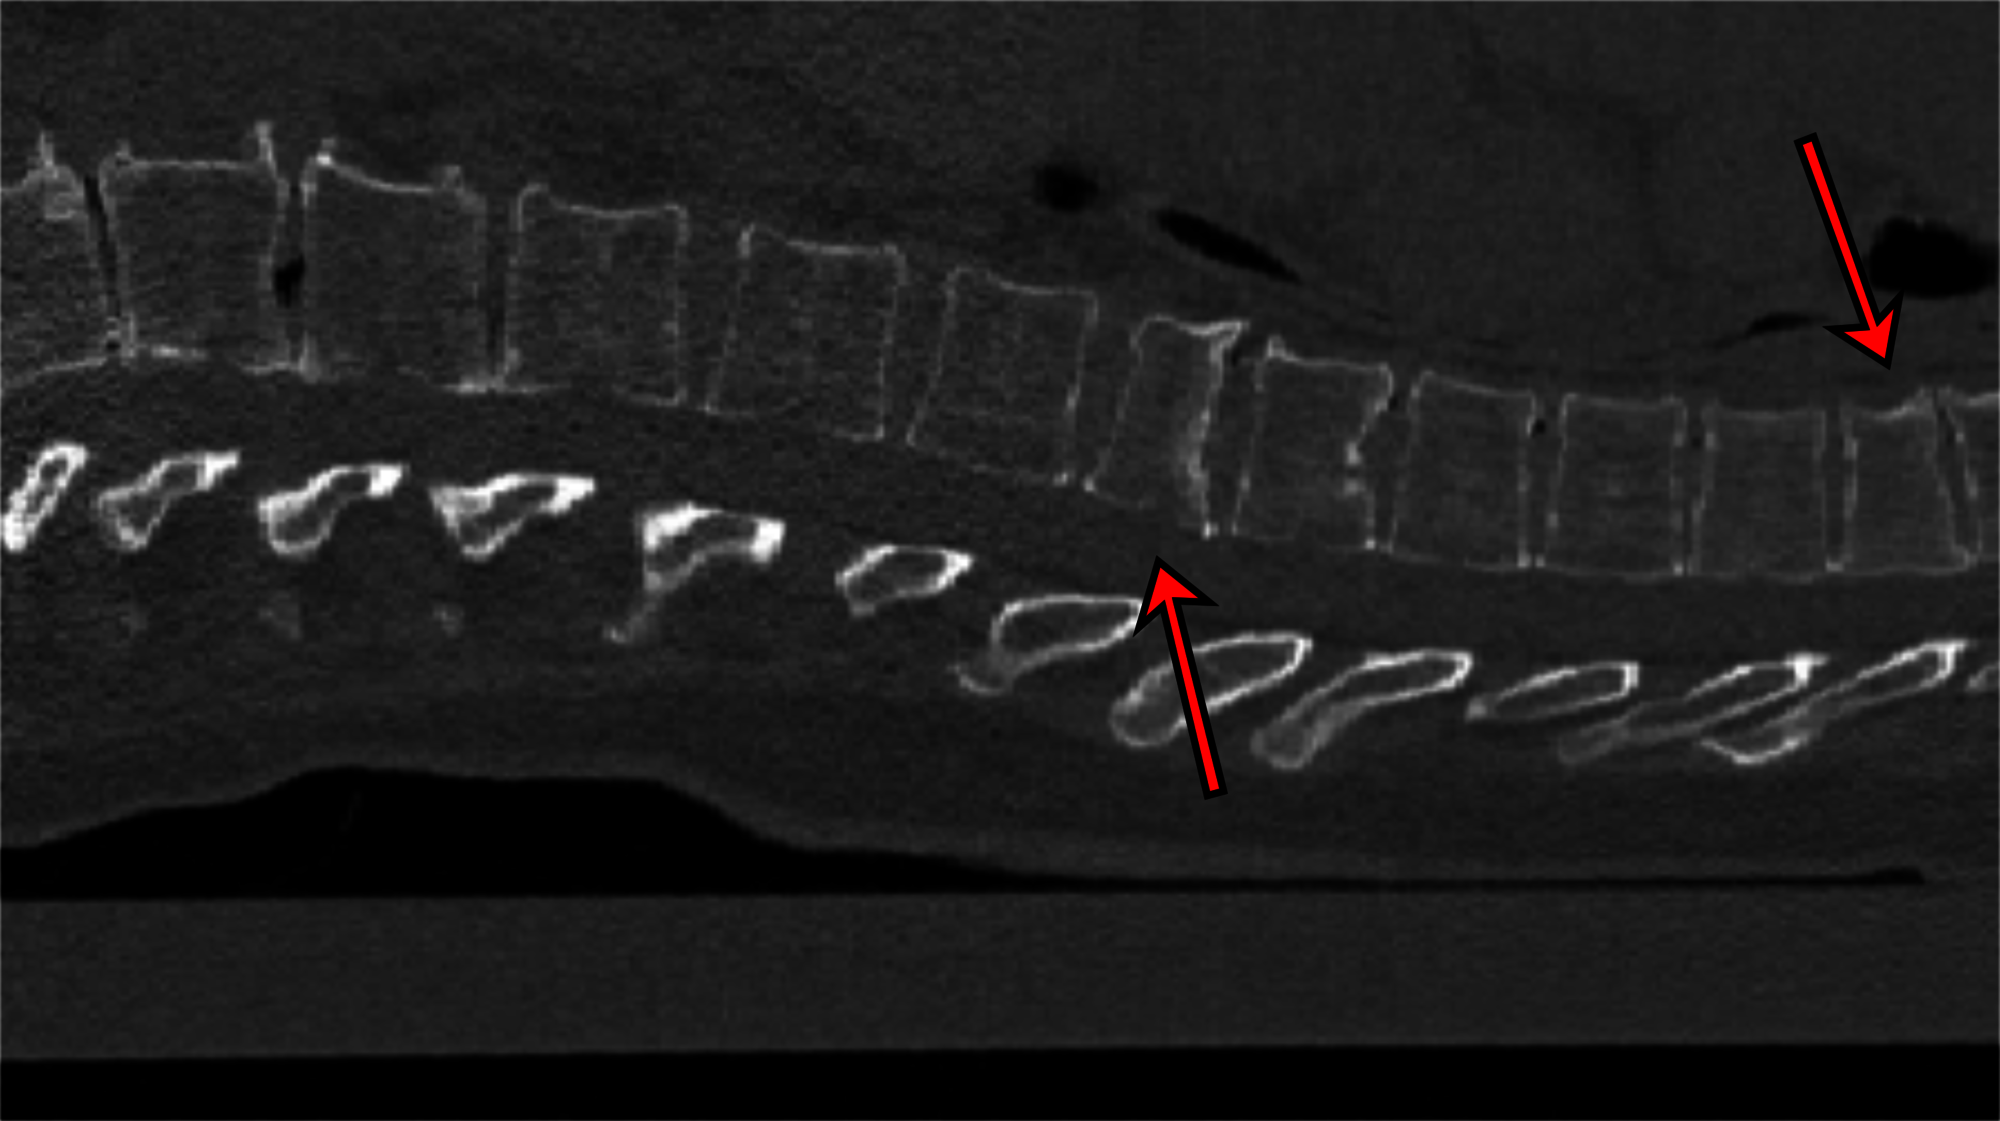

Osteoporose ist eine verbreitete Erkrankung in Deutschland. Laut Bone Evaluation Study ergaben sich hierzulande hochgerechnet etwa 6,3 Mio. Osteoporose-Betroffene. Die Zahl der Neuerkrankungen wurde auf 885.000 jährlich geschätzt. Doch nach wie vor bleibe die Krankheit oft unerkannt, so der Bundesselbsthilfeverband für Osteoporose. Und 80 Prozent der Osteoporosepatienten seien Frauen, was oft am gesunkenen Östrogenspiegel nach den Wechseljahren liege. Auch insgesamt baut sich im Alter die Knochensubstanz vieler Menschen ab. Die WHO geht davon aus, dass sich die Anzahl der Knochenbrüche aufgrund von Osteoporose bis 2050 weltweit vervierfachen werde. In nicht seltenen Fällen kommt es auch zu Brüchen an den Wirbelkörpern. Mittels Röntgenuntersuchung oder Computertomografie (CT) könnten Wirbelfrakturen zwar nachgewiesen werden, aber dazu komme es nicht immer, so die Wissenschaftler/-innen an der der Christian-Albrechts-Universität zu Kiel (CAU). Zum Beispiel weil das CT aus anderen Gründen gemacht und ein Wirbelbruch im Alltagsstress in der Klinik übersehen werde.

Oft würden CT-Bilder vom Brustkorb aufgenommen, um zum Beispiel die Lunge anzuschauen. Die Wirbelsäule sei zwar auf dem Bild zu sehen, werde aber nicht geprüft, weil vielleicht ein anderes Problem im Vordergrund stehe. „Unser Programm kann bei solchen Untersuchungen im Hintergrund laufen. Es schaut sich automatisch die Wirbelsäule an und gibt einen Hinweis auf Frakturen der Wirbelkörper, die ansonsten vielleicht nicht entdeckt worden wären“, erklärt Erstautor Yilmaz. Das sei wichtig, denn das Vorhandensein von Wirbelfrakturen erhöhe das Risiko weiterer Brüche erheblich. Die Software arbeite mit sogenannten neuronalen Netzen. An 159 CT-Bildern der Wirbelsäule, die aus sieben Krankenhäusern Deutschlands stammten, wurde die KI getestet. Erfahrenen Radiologinnen und Radiologen begutachteten zuvor die Bilder und entdeckten 170 Frakturen. „90 Prozent der Fälle mit Frakturen klassifizierte das neuronale Netz korrekt sowie 87 Prozent der Wirbel ohne Frakturen“, berichtet Yilmaz.